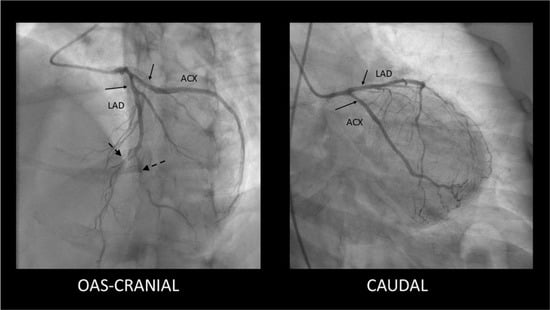

- SCAD Type 2—long, diffuse, usually tubular lesion, longer than 20–30 mm, without a visible intimal flap or double lumen. The Type 2 lesion does not ameliorate after intracoronary nitroglycerine administration (in contrast with coronary spasm). This type is the most common angiography pattern, being present in over half of SCAD cases (60–70%) [,,] (Figure 2). Figure 2. Type 2 SCAD lesions—mild, smooth stenoses located in the proximal segments of the LAD and Cx coronary arteries (solid arrows) along with distal occlusions in LAD and diagonal branch (dashed arrows). Figure 2. Type 2 SCAD lesions—mild, smooth stenoses located in the proximal segments of the LAD and Cx coronary arteries (solid arrows) along with distal occlusions in LAD and diagonal branch (dashed arrows).